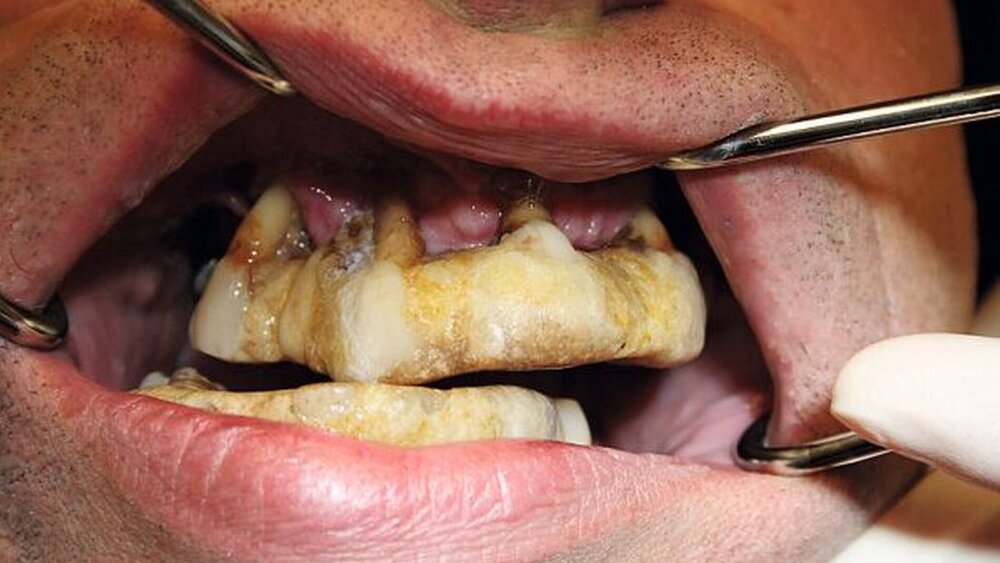

Der Patient stellte sich in der Praxis initial im April 2008 vor, nachdem er laut eigener Aussage ganze zwölf Jahre nicht in zahnärztlicher Behandlung war.

In den 90er-Jahren sei eine mehr oder weniger erfolgreiche Parodontaltherapie erfolgt, die eine Stabilisierung der Zähne mittels einer gegossenen Schiene im Oberkiefer inkludierte. Mit auftretender Lockerung oder dem Herausbrechen einzelner Zähne klebte der Patient diese mit Sekundenkleber in einen über die Jahre entstehenden Komplex aus Sekundenkleber und Zahnstein wieder ein. Der Patient kaute demnach auf einer neugeschaffenen Okklusion und schuf sich ein künstlich neues Profil.